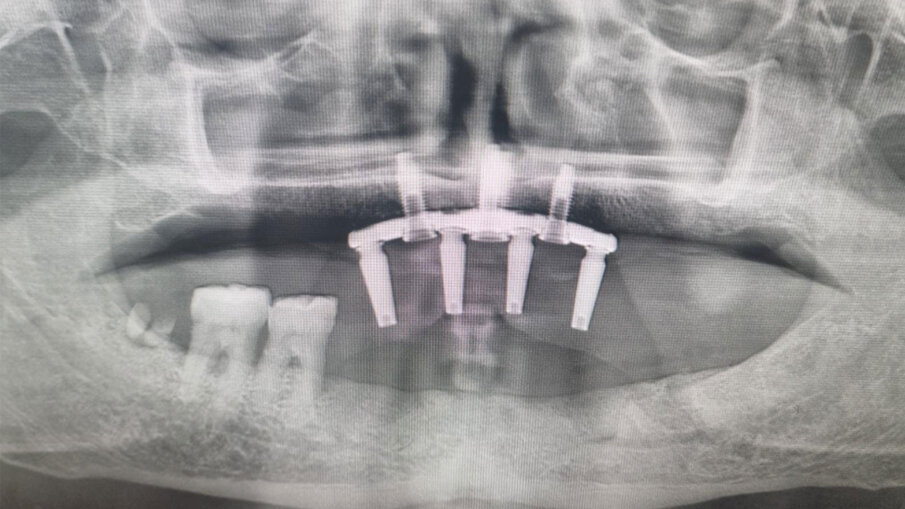

Il dispositivo presenta quattro alloggiamenti per impianti di piccole dimensioni (3,3 mm) e di lunghezza variabile tra 8 e 12 mm. Se consideriamo lo spessore del dispositivo diciamo che gli impianti dovrebbero essere collocati a una profondità non superiore ai 4 mm. I punti precisi di fissazione sarebbero, con l’ultimo disegno del PD, uno anteriore nella parte più nucale della spina nasale anteriore e uno più nucale nella parte iniziale della zona in cui il vomere si incastona con il versante nasale della sutura palatina mediana. Gli altri due sono rispettivamente nel primo e secondo quadrante in corrispondenza delle suture della premaxilla con le ossa mascellari. La testa degli impianti è progettata per restare una frazione di millimetro sotto la superfice del dispositivo.

Lo spessore della struttura del PD presenta 44 microfori passanti che permettono allo stesso di non fare effetto barriera tra l’osso basale e il periostio sovrastante. I dispositivi si distinguono in “a carico immediato” con i monconi monolitici senza connessioni da protesizzare subito; ed “a carico differito” cioè senza monconi ma con alloggiamenti filettati per permette di avvitare in un secondo momento quattro monconi per la protesizzazione (Fig. 1). Il procedimento chirurgico prevede una minima incisione da canino a canino, scheletrizzazione con distacco della parte terminale del nervo nasopalatino, come tutti i sottoperiostei, la modellazione dell’osso residuo con piezosurgery o fresoni per accogliere la forma del dispositivo ad appoggio completo e fissazione con impianti ridotti come detto sopra. La sutura sarà a completa copertura del PD a seconda se a carico immediato o differito prevede una seconda apertura solo sulle connessioni dei monconi che hanno delle viti tappo inserite (Figg. 2-15).

Fig. 7 - RX dopo l’inserimento del Premaxillary Device.

Fig. 10 - RX dopo 3 Mesi. Si è proceduto con l’inserimento dei monconi più provvisorio fisso.